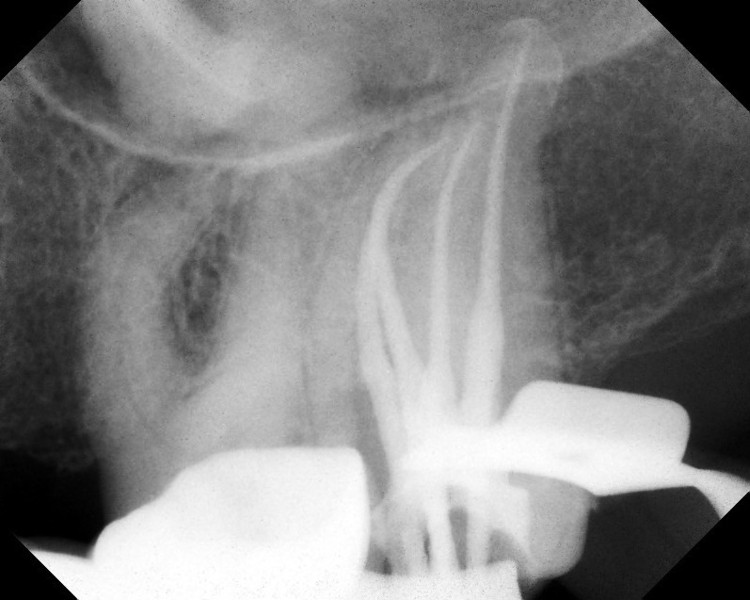

In meiner Fachpraxis für Zahnerhaltung führe ich sowohl Revisionen als auch Behandlungen der verschiedenen Komplikationen, wie Instrumentenbrüche, Perforationen. Kanal- bzw. Apextransportationen, Stufen usw. durch.

Digitales Röntgen wurde 2006 zur Strahlungsreduktion und Qualitätssicherung eingeführt !